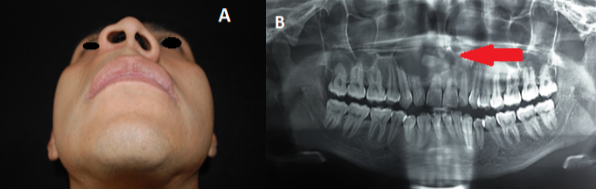

Hallazgos clínicos extraorales:

Se observó un acrecentamiento del volumen en el tercio medio facial del lado derecho en zona nasogeniana, con elevación de la fosa nasal derecha y ausencia del surco nasogeniano ipsilateral. El paciente se refiere completamente asintomático (Ver Figura 1A).

Examinación radiográfica:

en la ortopantomografía se identificó fórmula dentaria completa, un área radiolúcida, unilocular, de bordes definidos, con unas dimensiones de aproximadamente 3 x 2.5 cm de un patrón circunferencial con respecto a sombra radiopaca en su interior, compatible con un diente supernumerario en el sector anterior del cuadrante superior derecho. Cabe mencionar que se observó rizolisis en los dientes: incisivo central superior derecho (N.11), incisivo lateral superior derecho (N.12) e incisivo central superior izquierdo (N.21) (Ver Figura 1B).

A. Fotografía caudo-cefálica.

B. Ortopantomografía.